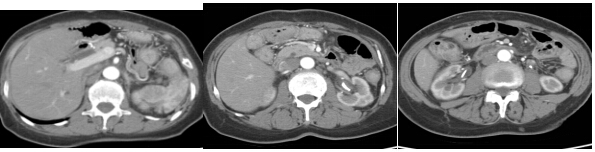

图3 2015年1月9日,三疗程DCF方案化疗后的腹部CT

2015年1月9日复查CT示:1.“胃癌术后”改变,食管空肠吻合口下游局部肠壁增厚。腹腔大网膜区域、肠系膜和腹主动脉旁散在淋巴结。结肠肝曲至脾曲肠壁广泛增厚。2.比较治疗前,后腹膜肿瘤浸润表现及淋巴结肿大并没有明显改善。同时,肿瘤标志物较前仍有不同程度升高。

图4 2015年4月1日二线治疗后的腹部CT

2015年4月1日复查CT:1.“胃癌术后”改变,食管空肠吻合口下游局部肠壁增厚。腹腔大网膜区域、肠系膜和腹主动脉旁散在淋巴结。部分结肠肠壁稍增厚。2.双侧尿路D-J管留置,肾周和输尿管周围少量渗出。CA199与AFP较前下降,CEA仍有所升高。